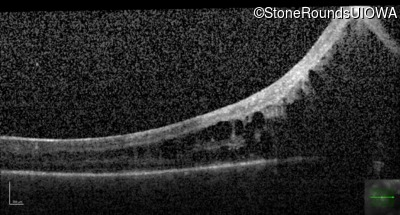

Optical Coherence Tomography - Right - Hand Motion

Exemplar / OCT Stack

OCT Stack